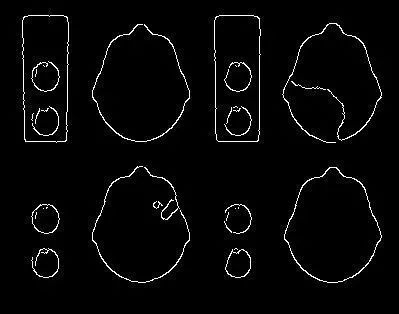

边缘检测过程的输出如下所示:

使用Canny算法的边缘检测输出

请注意,尽管已识别出脑图片段,但仍有许多不需要的边缘需要消除,并且某些边缘之间有间隙需要封闭。

解决这个问题的一种常用方法是形态转换,它涉及在图像上使用一系列的扩张和腐蚀来去除不需要的边缘和闭合间隙。

我们在多次迭代中使用OpenCV函数“ dilate()”和“ erode()”来获得如下输出。

使用OpenCV对边缘进行了一些增强

如我们看到的那样,边缘现在已经完成并且比以前光滑得多。